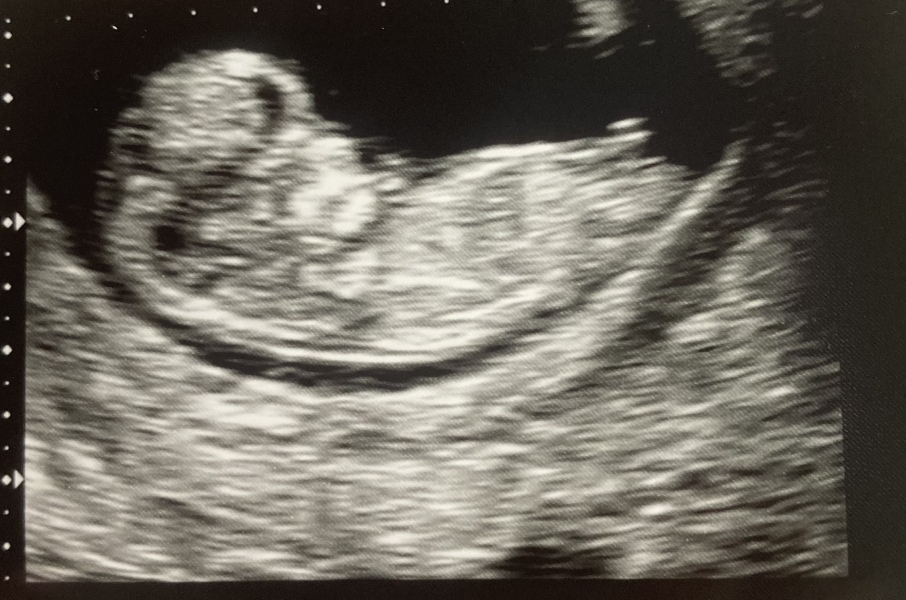

Ttcsecond · 13/07/2023 13:19

@Angelselevenx

Scan went well. Measuring 9 weeks and heartbeat of 170. Was really nervous before but everything looked perfect. Although the pictures are rubbish 🤣.

how are you?

xx